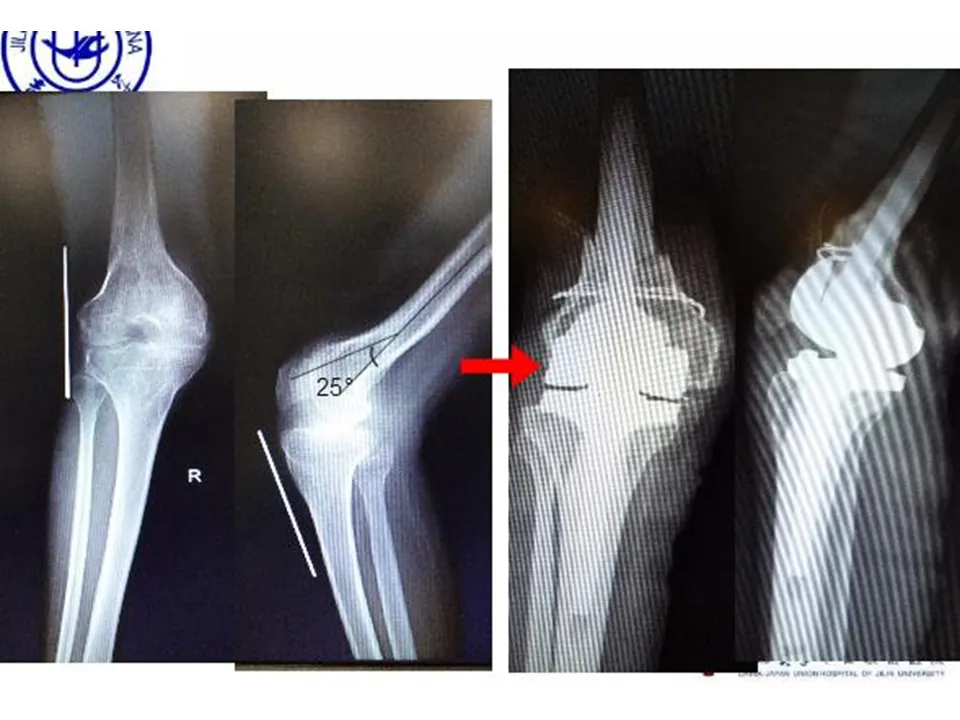

>【骨科PPT】全膝关节置换的截骨原则

【骨科PPT】全膝关节置换的截骨原则